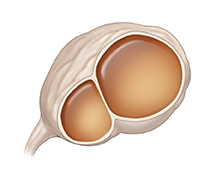

Benign cystadenoma

If the capsule around the ovary grows and fills with fluid, it can form a cystadenoma. These cysts can grow on one or both ovaries. Often they cause no symptoms if they are small. But if they become large, they can press on organs near the ovaries, causing pain. They can also cause pain by stretching the ovarian capsule. A cyst that pushes on the bladder can cause frequent urination. Sometimes these cysts break open and bleed.